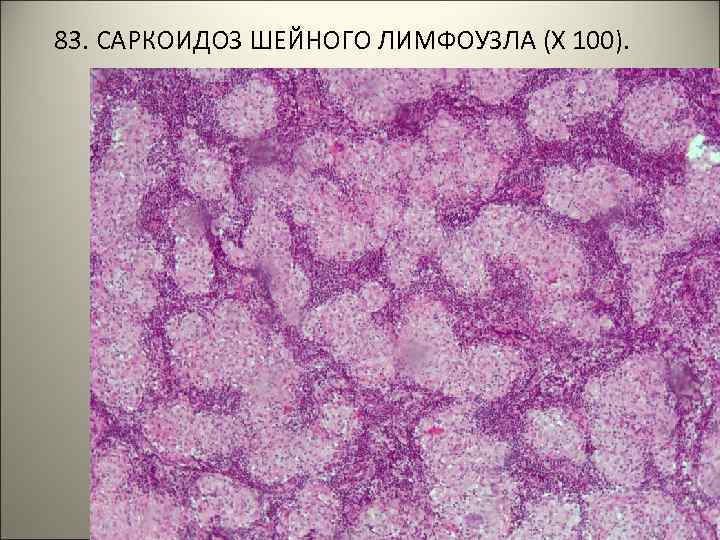

• 83. САРКОИДОЗ ШЕЙНОГО ЛИМФОУЗЛА. • В ткани лимфоузла множественные гранулемы, состоящие из эпителиоидных, лимфоидных, единичных гигантских клеток. Творожистый некроз отсутствует, границы гранулем четкие (т. н. «штампованные» гранулемы).

83. САРКОИДОЗ ШЕЙНОГО ЛИМФОУЗЛА (Х 100).

83. САРКОИДОЗ ШЕЙНОГО ЛИМФОУЗЛА (Х 400).